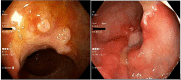

Klippel-Trenaunay Syndrome (KTS) is a rare genetic vascular disorder characterized by a limb affected by varicose veins, port wine stains, and hypertrophy of bone and soft tissue. It can also present with vascular malformations in the gastrointestinal tract, liver, spleen, genitourinary tract, and heart. We present a 27-year-old case of KTS diagnosed in adulthood associated with recurrent venous thromboembolism and gastrointestinal bleeding.